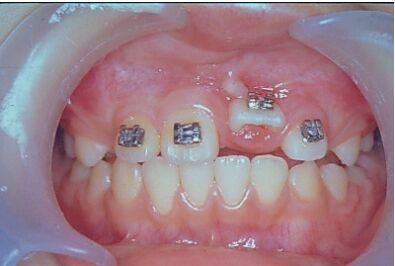

14.如圖所示,左上正中門齒延遲萌出(delayed eruption),將該牙手術暴露黏上矯正器後,下列何種矯正牽引的方式最為適合? (A)使用14 mil NiTi 圓線放入所有有黏矯正器的牙齒,含左上正中門齒 (B)使用16 × 22 mil不鏽鋼角線放入所有有黏矯正器的牙齒,含左上正中門齒 (C)使用16 × 22 mil不鏽鋼角線放入其他矯正器,並使用14 mil NiTi 圓線牽引左上正中門齒 (D)使用14 mil NiTi圓線放入其他矯正器,並使用16 × 22 mil不鏽鋼角線牽引左上正中門齒